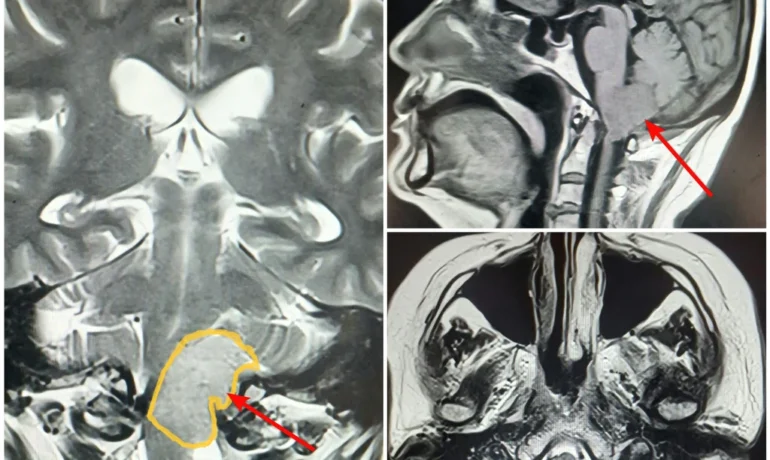

Менингиома операциядан олдин

Neurolife марказида ташхисни аниқ қўйиш ва операцияни хавфсиз режалаштириш учун комплекс диагностик ёндашув қўлланади. Мия ўсмаси МРТ текширувининг асосий босқичи ҳисобланади. Магнит-резонанс томография ўсманинг ўлчами, тузилиши ва атроф тўқималар билан ўзаро муносабатини аниқлаш имконини беради.

Қўшимча равишда мия ўсмаларининг нурли диагностикаси қўлланади, жумладан краниовертебрал ўтиш соҳасининг МСКТ текшируви ҳам ўтказилади, бу суяк тузилмаларини баҳолаш ва хавфсиз жарроҳлик кириш йўлини танлаш учун зарур. Шу тариқа, асосий диагностик усуллар қуйидагилар:

- контраст билан мия ва бўйин умуртқа қисми МРТ;

- краниовертебрал ўтиш соҳасининг МСКТ.